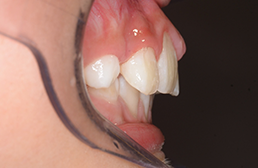

| 主訴 | 上顎前歯のでこぼこ | 診断名 | アングルⅡ級叢生症例 | ||||

|---|---|---|---|---|---|---|---|

| 初診時年齢 | 6歳9ヵ月 | 性別 | 男 | 動的治療期間 | 6ヵ月 | ||

| 既往歴として上顎正中過剰歯(2本)は抜去済み。その影響で上顎右側中切歯は捻転して萌出しており、下顎右側中切歯と早期接触が認められたため2x4(上顎のみブラケット装着)にて前歯部の改善を行った。現在は永久歯列完成まで経過観察を行い、希望があれば口元の突出感を改善するために本格矯正治療を行うことにしている。 | |

| セファロ所見 | 上下顎骨は調和のとれた位置関係を示していたが、頭蓋に対して両顎共に前方に位置していた。上下顎前歯は唇側傾斜していた。 |